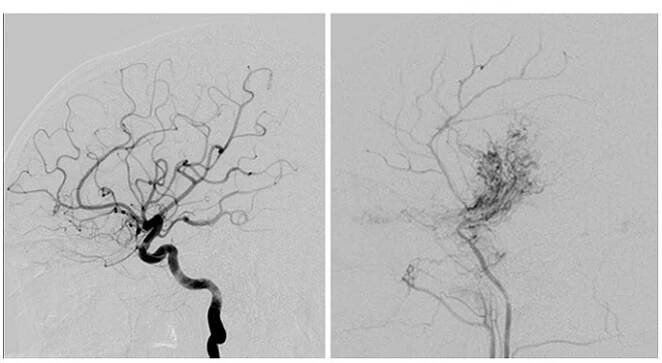

Ischemie mozku – Wikipedie

Ischemie mozku (také mozková či cerebrální ischemie) je porucha prokrvení mozku, kvůli tomu má orgán nedostatek kyslíku a postupně odumírá.

Cévní onemocnění mozku | Neurochirurgická a neuroonkologická…

Cévní onemocnění mozku jsou skupinou onemocnění v naší zemi velmi rozšířených. Tento vysoký výskyt souvisí především s naším životním stylem (nezdravá strava, málo pohybu, kouření, pití alkoholu).